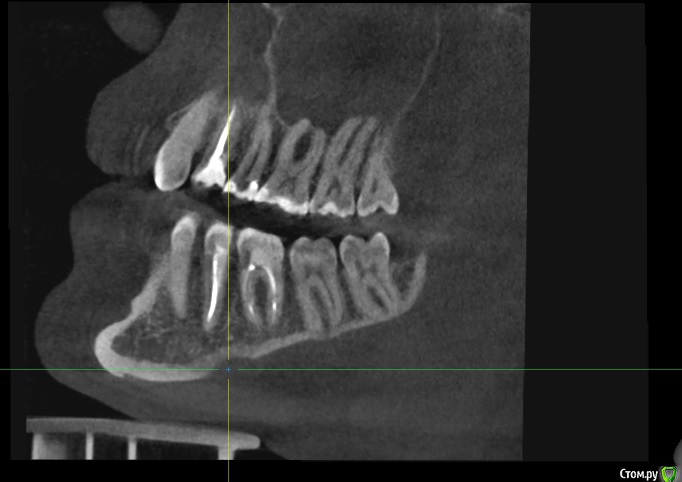

Илья Т. Опубликовано 24 июня, 2020 Поделиться Опубликовано 24 июня, 2020 (изменено) Добрый день! 3 месяца назад была проведена имплантация 21 зуба, до этого за еще за 3 месяца был удален этот зуб и в лунку заложен костный материал (т.к имплантолог изучив КТ сказал что кости не много и сверху находится пазуха, необходимо подсыпать костный материал туда). 1 июля идти с КТ на слепки, сделав вчера КТ решил посмотреть его сам и меня смутило, что в некоторых положениях справа от имплантата (где нёбо) как бы пустота? А когда подкрутив колесико на мышке как бы меняется резкость, то она пропадает? Можно ли по скринам определить нормально ли интегрировался имплантат и нормальный ли объем костной ткани? Изменено 24 июня, 2020 пользователем Илья Т. Ссылка на комментарий

Irouil Опубликовано 24 июня, 2020 Поделиться Опубликовано 24 июня, 2020 Пустота - скорее всего просто засветка от имплантата. Снимки выглядят нормально. Интеграция имплантов проверяется не по снимкам 3 Ссылка на комментарий

Илья Т. Опубликовано 2 июля, 2020 Автор Поделиться Опубликовано 2 июля, 2020 Снимки выглядят нормально.А подскажите ещё с фронтальной части достаточно объема кости? Просто где то прочитал, что чтобы имплантат долго стоял необходимо сколько то миллиметров кости вокруг него чтобы было обязательно... Ссылка на комментарий

red_butler Опубликовано 2 июля, 2020 Поделиться Опубликовано 2 июля, 2020 А подскажите ещё с фронтальной части достаточно объема кости? ДОСТАТОЧНО 1 Ссылка на комментарий